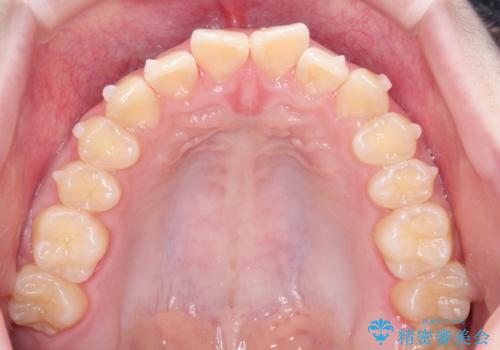

なるべく通院回数を減らして矯正したい インビザラインでのガタガタ矯正

- 上下の歯並びを治したいとのことで来院されました。

受験生ということもあり、なるべく通院回数を減らしての矯正を希望されたので、インビザラインで治療をすることにしました。